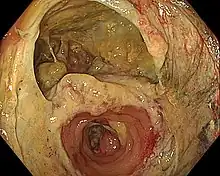

A surgical anastomosis is a surgical technique used to make a new connection between two body structures that carry fluid, such as blood vessels or bowel. For example, an arterial anastomosis is used in vascular bypass and a colonic anastomosis is used to restore colonic continuity after the resection of colon cancer.

- Gastrointestinal (GI) tract: Esophagus, stomach, small bowel, large bowel, bile ducts, and pancreas. Virtually all elective resections of gastrointestinal organs are followed by anastomoses to restore continuity; pancreaticoduodenectomy is considered a massive operation, in part, because it requires three separate anastomoses (stomach, biliary tract and pancreas to small bowel). Bypass operations on the GI tract, once rarely performed, are the cornerstone of bariatric surgery. The widespread use of mechanical suturing devices (linear and circular staplers) changed the face of gastrointestinal surgery. A suture-free method for anastomosis of the colon to colon or rectum has been developed.[1][2]